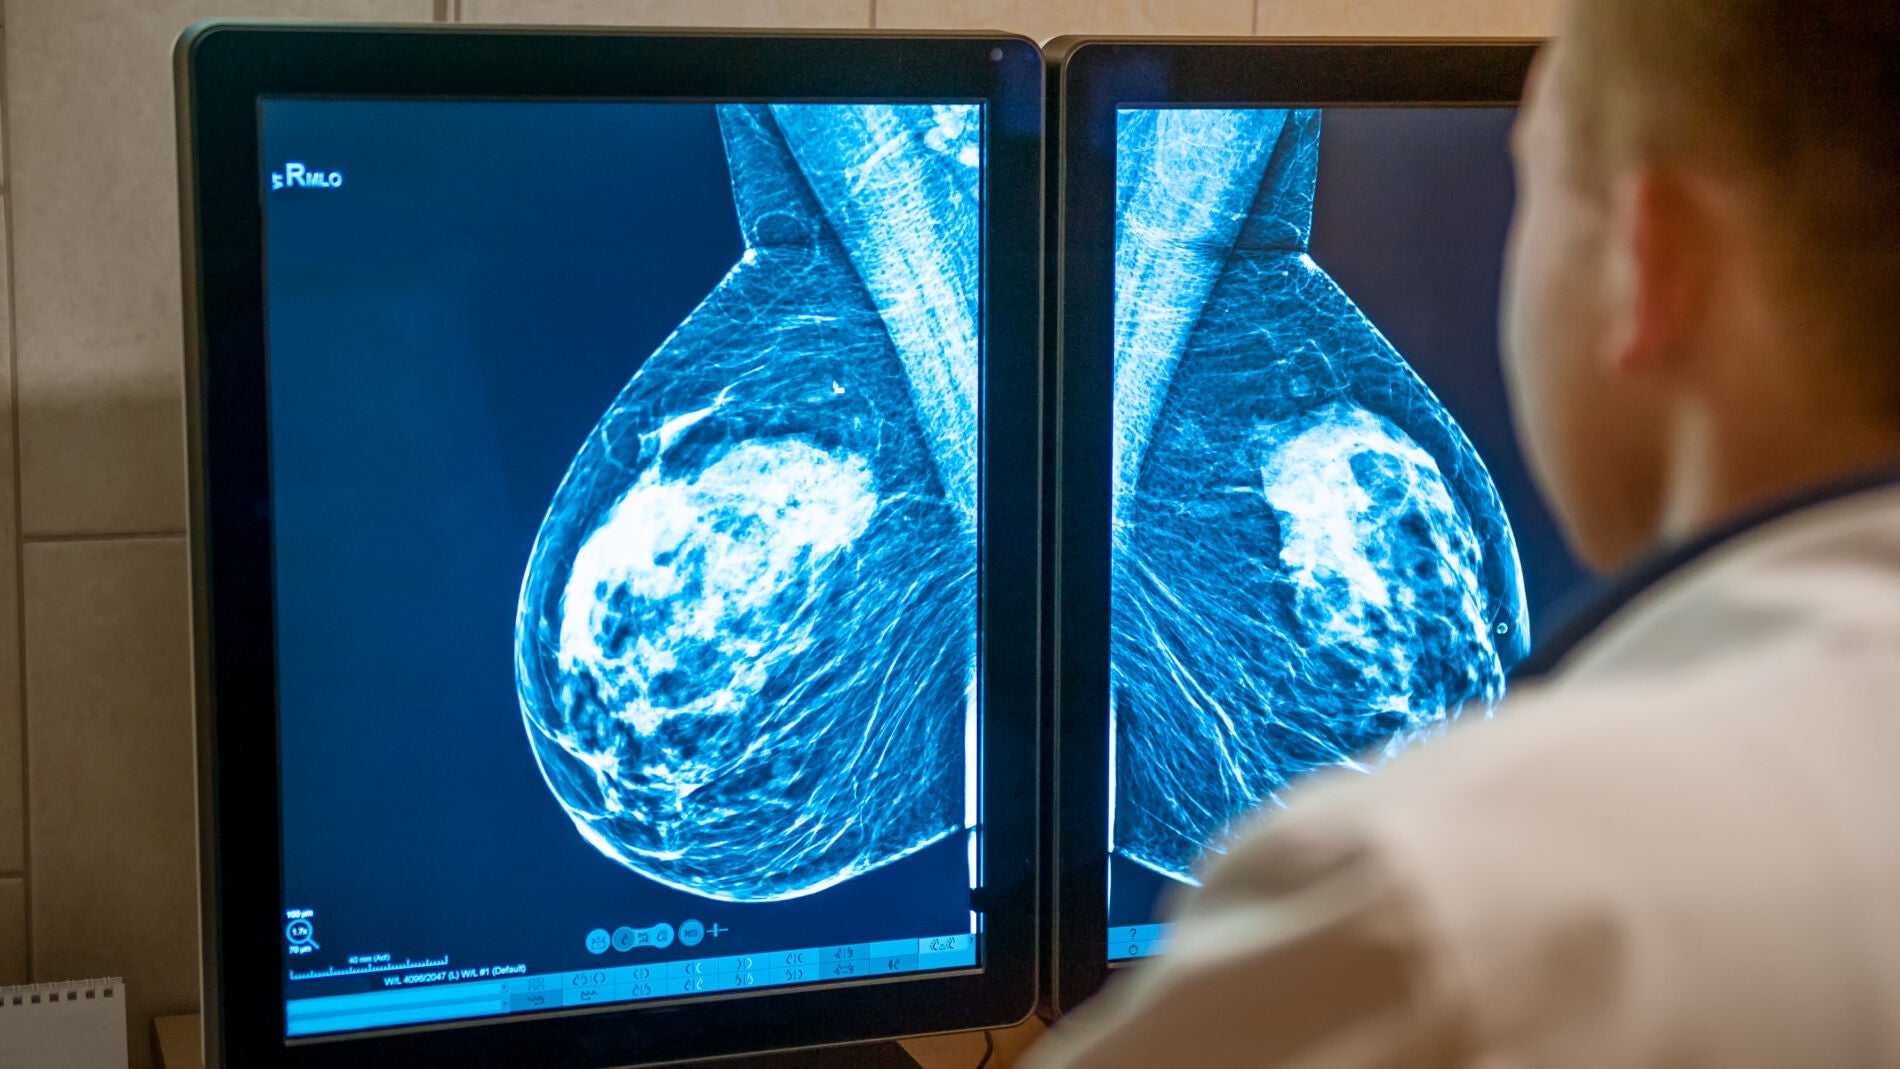

Cada hora, 4,3 mujeres serán diagnosticadas este año de cáncer de mama en España. No todas necesitarán quimioterapia para reducir el riesgo de que el cáncer reaparezca. De hecho, aunque la quimioterapia sigue siendo un tratamiento eficaz y necesario para algunos casos, las pautas de tratamiento han cambiado y van a seguir cambiando, de modo que no se recomienda hoy a tantas personas como hace 20 años y en el futuro se indicará a muchas menos.